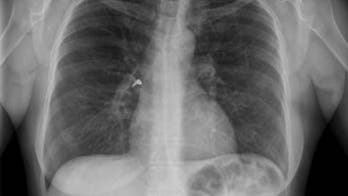

October 26, 2015 Woman accidentally gets earring stuck in lung after using inhaler A woman in Australia had an unexpected medical emergency on New Year's Eve after she accidentally inhaled one of her earrings, according to a new case report.